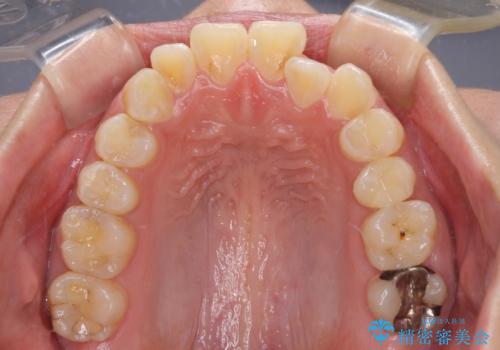

- 前歯のクロスバイトと、口元が閉じにくいとのことで来院された患者様です。

口元の突出感を改善する必要があるため、上下左右の第1小臼歯4本を抜歯し、ワイヤー装置にて矯正治療を行うこととしました。

むし歯のリスクが高かったため、治療が長期化しないように心がけました。

当初の予定通り、2年強で無事に治療を終えることができました。